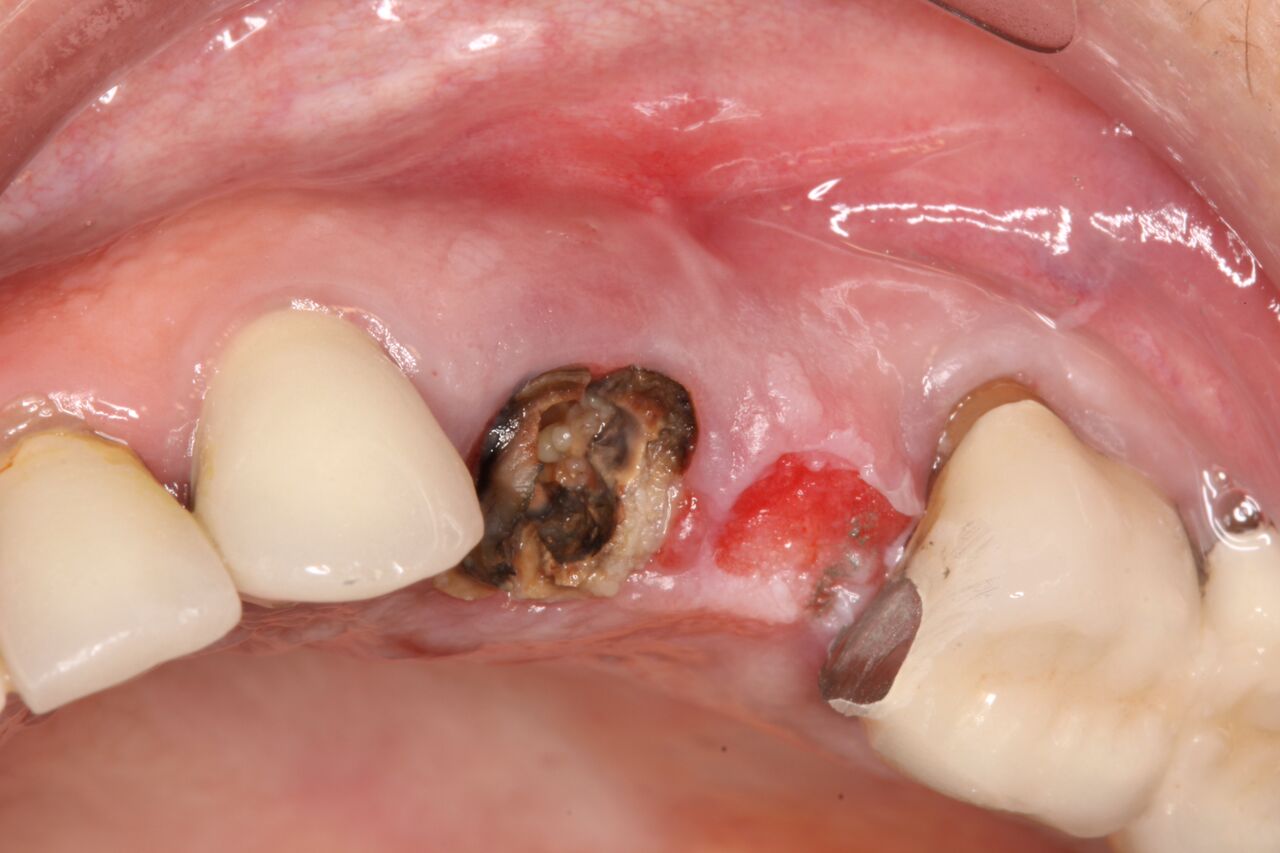

(10.) Initial clinical evaluation of Nos. 12 through 14 after crown on No. 12 and pontic on No. 13 removed.

Figure 10

(11.) Extraction of fractured and decayed No. 12 with periapical granuloma and original

Figure 11

(12.) Extraction of fractured and decayed No. 12 with periapical granuloma and original

Figure 12